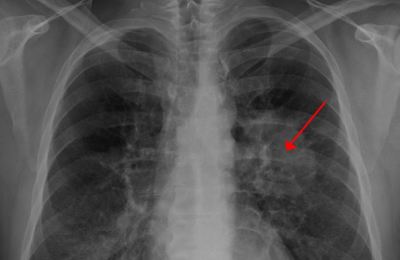

폐암은 원발성 폐암을 말하며 원발성 폐암은 폐에서 기원하는 악성 종양을 말한다. 폐로 전이된 암은 폐로 전이된 것으로 분류되며, 폐암이라기 보다는 기원 장기로 전이된 것으로 분류된다. 폐암은 조직학적 유형에 따라 크게 소세포폐암과 비소세포폐암으로 분류된다.

이러한 폐암의 원인으로 인해 폐암으로 진단되기 전에 폐암 초기증상을 조기에 발견하면 다른 장기로의 전이나 진행성 폐암으로의 진행을 어느 정도 지연시키거나 적절하게 치료할 수 있지만 일반적으로 폐암의 초기 단계는 특별한 징후나 증상이 없으므로 조기에 발견하는 경우는 극히 드뭅니다.

폐암 초기에는 기침이 잦거나 가래가 끓는 등 감기와 같은 증상이 나타날 수 있다. 따라서 폐암은 초기에 암인지 판단하기 어렵다. 또한 객담이나 적혈구를 동시에 토하는 것도 폐암을 진단하는 가장 중요한 증상 중 하나이다. 붉은 피가 섞인 가래 증상이 있으면 병원에 가서 검사를 받아야 한다.